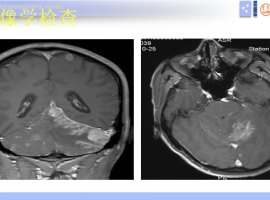

肺腺癌脑转移3年,长期口服奥西替尼,PET-CT提示左侧上牙槽骨转移

肺腺癌脑转移3年,长期口服奥西替尼,EGFR19突变,PET-CT提示左侧上牙槽骨转移,肺部结节增多增大。一个月前加用卡博替尼2粒,早上卡博,下午奥西。一个月后复查胸部CT结节较前明显缩小。但是患者体感没有变好,现在 ...